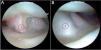

– A) Visión artroscópica proximal de la articulación mediocarpiana desde el portal MC-U. 1: piramidal distal; 2: semilunar distal; 3: escafoides distal; 4: hueso grande proximal; 5: articulación escafolunar distal; 6: articulación lunotriquetal distal. B) Visión artroscópica distal de la articulación mediocarpiana desde el portal MC-U. 7: ligamento capitohamate; 8: ganchoso proximal.